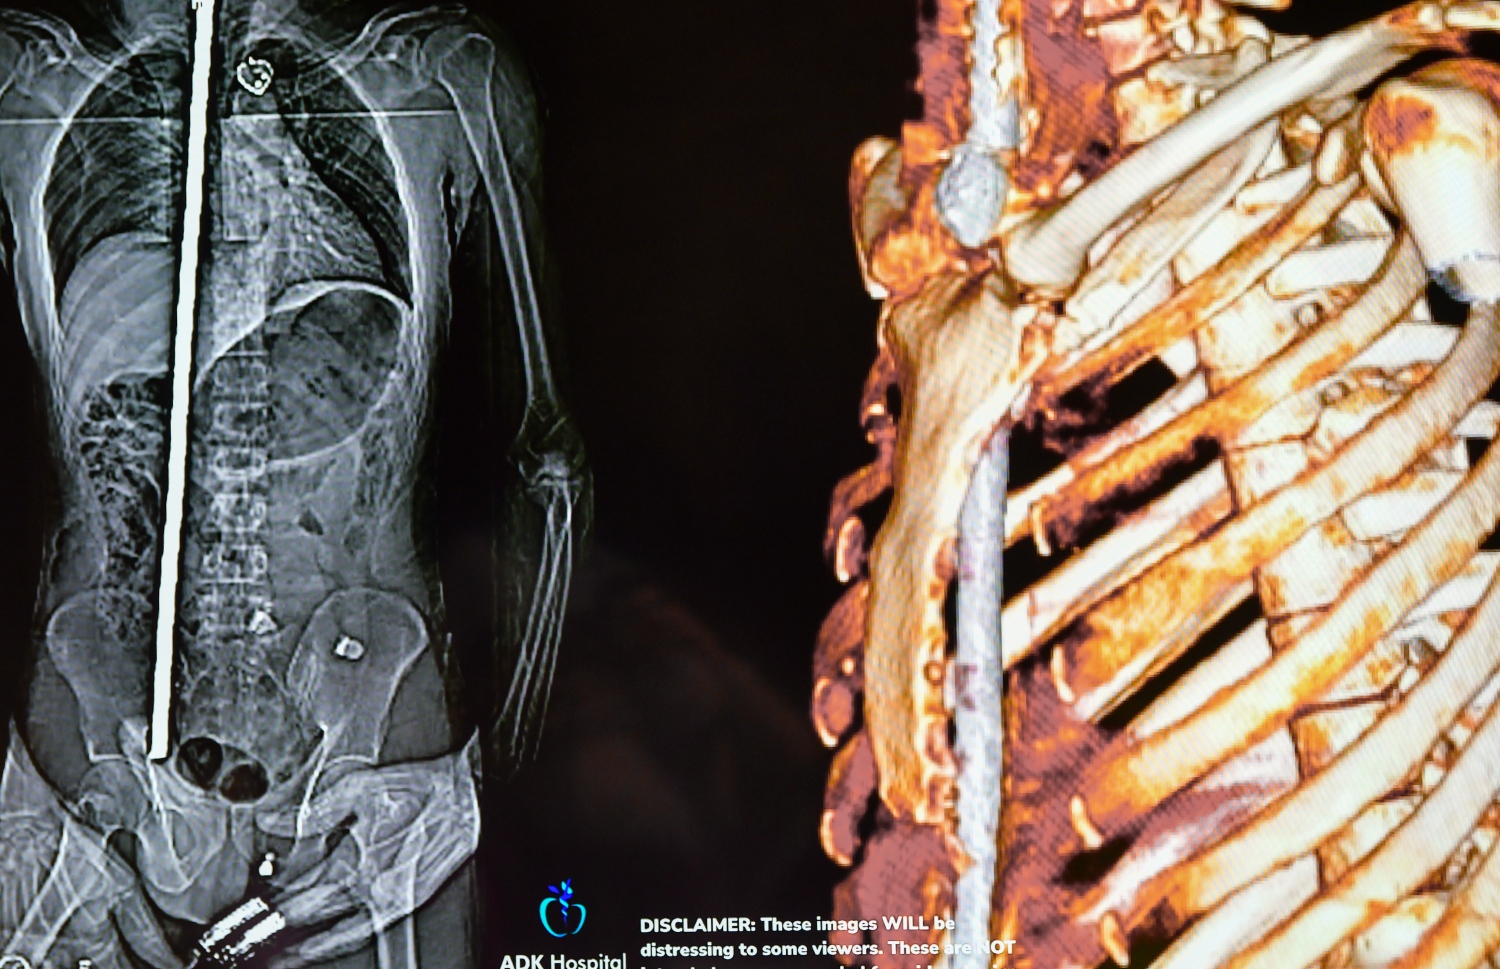

ޕޭޝަންޓުގެ ގަޔަށް އެ ދަނޑު ވަދެފައި އޮތް ގޮތުގެ ސްކޭން އަދި ތްރީޑީ ފޮޓޯތަކެއް ވެސް މިއަދު ދެއްކި އެވެ. އެ ފޮޓޯތަކުން ފެންނަ ގޮތުގައި، ނޭފަތުގެ މަތިން ހަށިގަނޑަށް ވަތް އެ ދަގަނޑު، މަތީތަލަ ފޫއަޅުވާލާފައި ކަރަށް ވަދެ، ފުރަތަމަ ގޮސް ޖެހެނީ މައިބަދައިގަ އެވެ. މައިބަދައިގައި ޖެހިފައި، ތިން ބަދަ ފުނޑުވެ އެވެ. އޭގެ ފަހުން ފުއްޕާމެ އަށް ވަދެ، ފުއްޕާމެ އާއި ބަނޑާ ދެމެދުގައި އޮންނަ މަސްގަނޑު ފޫއަޅުވާލައި ބަނޑުގެ އެތެރެއަށް ވަދެ، ފުރަމޭ އަށް ވެސް ގެއްލުންވެ އެވެ. އަދި ބަނޑުގެ މަސްގަނޑު ތެރެއަށް ވަދެގެން ގޮސް، އެ ދަނގަޑު ބުރި ހުއްޓެނީ އުކުޅުވަޅުގެ ކަށިގަނޑުގައި ޖެހިފަ އެވެ.

ހަށިގަނޑު ފޫއަޅުވާލައި، ދަގަނޑެއް ވަތް ބިދޭސީ މަސައްކަތު މީހާއާ ގުޅޭ މައުލޫމާތު ދިނުމަށް އޭޑީކޭ ހޮސްޕިޓަލުން ބޭއްވި ނިއުސް ކޮންފަރެންސްގައި ދެއްކި، އެ މީހާގެ ހަށިގަނޑަށް ދަގަނޑު ވަދެފައި އޮތްގޮތް ފެންނަ ގޮތުގެ ސްކޭނަކާއި ތުރީޑީ ފޮޓޯއެއް -- ފޮޓޯ: ފަޔާޒް މޫސާ | މިހާރު

ހަށިގަނޑު ފޫއަޅުވާލައި، ދަގަނޑެއް ވަތް ބިދޭސީ މަސައްކަތު މީހާއާ ގުޅޭ މައުލޫމާތު ދިނުމަށް އޭޑީކޭ ހޮސްޕިޓަލުން ބޭއްވި ނިއުސް ކޮންފަރެންސްގައި ދެއްކި، އެ މީހާގެ ހަށިގަނޑަށް ދަގަނޑު ވަދެފައި އޮތްގޮތް ފެންނަ ގޮތުގެ ސްކޭނެއް -- ފޮޓޯ: ފަޔާޒް މޫސާ | މިހާރު